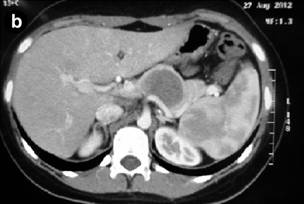

Computed Tomography (CT) of the Abdomen

CT of the abdomen (Figures 2) can identify a circumscribed lesion, usually single, encapsulated, with evidences of internal hemorrhage with tomographic heterogeneous aspects due to the presence of solid and cystic components in different amounts and predominance [1, 15, 16, 17]. Thus, the lesion can consist just of solid components and it can pass through the mixed or solid-cystic form (most common general tomographic presentation) and reach the purely cystic aspect [1, 15, 16, 17]. According to studies by Hu S et al. [16] and Park MJ et al. [15], there is different prevalence between the types of tomographic presentations of pancreatic SPN lesions regarding gender. Thus, the solid-cystic form is the most frequent in women and in men, the form consisting just of solid components prevails [15, 16]. Still, the contrast or understrapper (hyper-density of the image shown in the CT) will be stronger if the amount of existing solid component in the lesion is bigger [1, 15, 16, 17]. Other features able to be evaluated and identified through the CT are: calcification in the capsule, periphery or in the center of the lesion [1, 15, 16, 17]; pancreatic parenchyma around the lesion with normal aspect associated with the non-dilated pancreatic and/or bile ducts [1, 15, 16, 17]; and invasions of vascular structures and neighbor organs, as well as metastases [4, 5, 7]. Finally, the vascularization of the tumor itself is often avascular or little to modestly hyper-vascular, but it is rarely seen [5]. Yet, it is worth talking about the role played by PET-CT when handling pancreatic NSP patients. Unfortunately, there are just a few studies about the use of PET-CT to evaluate these patients. Thus, the few existing studies on this theme are retrospectives with small casuistic [21]. We highlight the uni-institutional retrospective study by Kim Y, et al. [21] which considers the recommendation of PET-CT to evaluate pancreatic NSP patients in order to identify the subtle metastases, especially when it assesses patients with a tumor formed by predominantly solid components.

|

Figure 2. a. Abdominal computerized tomography showing the SPN in the pancreatic head in Case #8. b. Abdominal computerized tomography after body-tail pancreatectomy with splenectomy for SPN (Case #7). |

Sixty percent (60%) of our patients were diagnosed with SPN of with the use CT and MRI scans of the abdomen (Table 2 and Figures 2a and 3). All the patients in our cohort had normal values of the following laboratory studies: complete blood count, coagulation panel (Prothrombin time; International normalized ratio; Partial thromboplastin time; Number of platelets; Bleeding time) amylase, serum creatinine, blood urea, serum albumin, liver profile and also had normal pre-operative tumor markers (like CEA and CA 19.9). The anatomic and pathological examination corroborated the diagnosis of SPN in 90% of the cases. Immunohistochemical studies were necessary to get the final diagnostic confirmation in only one case.

All patients in our 10-cases series underwent surgical treatment, the head of the pancreas (Table 2 and Figure 4a) and the pancreatic body (Table 2 and Figure 4b) were the usual location of the tumor. Consequently, the most common used therapeutic surgical procedures performed were: Whipple’s operation, performed for tumors in the head of the pancreas; and body-tail pancreatectomy with splenectomy, performed for tumors in the body and tail of the pancreas (Figures 2b and 5) (Table 2). It is worth emphasizing that two out of the 4 patients with tumor in the head of the pancreas; underwent Whipple’s operation along with vascular resection followed by reconstruction with splenic vein graft [15] and internal jugular vein patch (Table 2 and Figure 6). There was no death in this cohort (Table 2).